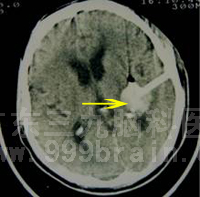

50岁的老王就是因为高血压引起突发脑出血昏迷被紧急送入广东三九脑科医院微侵袭神经外科救治的。入院行头颅CT检查见其左侧基底节区脑出血,出血量约为30ml。入院后,微侵袭神经外科 吴杰主任在详细了解其病情后,立即决定在局麻下为其行立体定下钻孔引流术,手术只花了30分钟,术程顺利,术后老王的神智得以明显改善。术后半个月复查CT检查见老王颅内血肿已基本消失,经过肢体功能锻炼,老王康复如常人,肢体运动功能没有因此受到影响。目前已康复出院。

钻孔引流术后改变。 术后复查CT见左基底节区脑出血完全吸收。